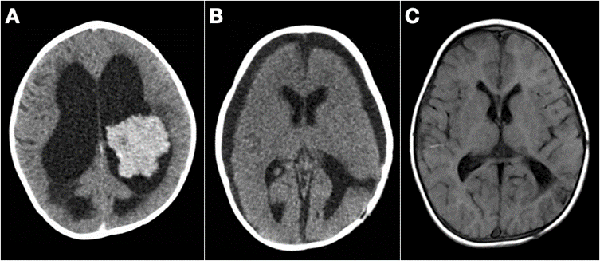

Figura 5: Tumores agresivos. A) Paciente de 8 meses de vida, sexo masculino, presentó irritabilidad, macrocefalia y somnolencia. TC de cerebro con contraste EV donde se observó imagen en región pineal que se extiende al tercer ventrículo. Se realizó cirugía de exploración, exéresis parcial, anatomía patológica informó pineoblastoma, paciente falleció a los 5 meses por progresión de la enfermedad. B) Paciente de 2 meses de vida, sexo masculino, consultó por deterioro progresivo del sensorio. TC de cerebro con contraste EV que evidenció lesión centroencefálica e hidrocefalia obstructiva. Se realizó cirugía de exploración de lesión, con colocación intraquirúrgica de drenaje ventricular al exterior. Anatomía patológica informó tumor embrionario indiferenciado. Paciente falleció a los 14 días por progresión de enfermedad. C) Paciente de 19 meses de vida, sexo femenino, consultó por vómitos a repetición. IRM de cerebro con contraste EV que mostró tumor supratentorial intraventricular con realce homogéneo con el contraste EV. Se realizó cirugía de exploración, con exéresis parcial por el intenso sangrado. Anatomía patológica informó carcinoma de plexos coroideos. Paciente fallece a los 3 meses.

Figura 7: A) Paciente de 13 meses, sexo masculino, consultó por alteraciones en la motricidad. TC de cerebro con contraste EV que evidenció lesión intraventricular que realza homogéneamente e hidrocefalia, se colocó DVE previo a cirugía de exéresis tumoral. B) TC de cerebro luego de cirugía, diagnóstico de papiloma de plexos coroideos, se retiró el DVE a las 48 hs. TC de cerebro de control al año con colecciones subdurales crónicas. Se decidió conducta expectante de las mismas. C) IRM de cerebro control a los 3 años, sistema ventricular de tamaño normal, corticotomía cerrada. Paciente sin secuelas neurológicas.

Figura 8: A y B) Paciente de 21 meses de vida, sexo femenino, que presentó hemiparesia faciobraquiocrural derecha, vómitos y deterioro del sensorio, TC de cerebro con contraste EV, lesión supra e infratentorial, con gran efecto de masa con compresión del tronco del encéfalo. Se realizó cirugía de exploración y exéresis parcial. Anatomía patológica informó papiloma de plexos coroideos. C y D) IRM de cerebro con contraste EV que evidenció resto tumoral intraventricular y en relación a cisternas peri mesencefálicas. Se realizó re exploración del tumor. E y F) Imagen por TC de cerebro con contraste EV postquirúrgica inmediata que evidenció exéresis total.